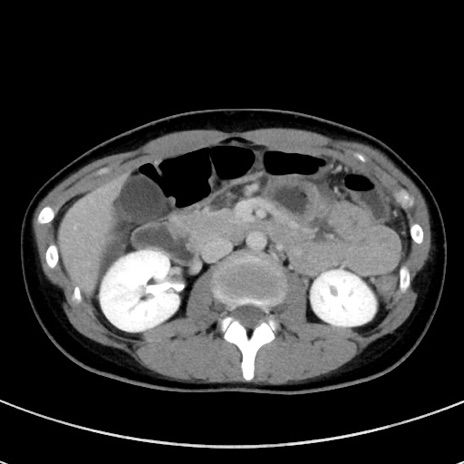

冠状断像

【症例】20歳代女性

【主訴】嘔吐、下腹部痛

【現病歴】昨日夕食後に嘔吐し下腹部痛が出現。本日になっても嘔吐持続し改善しないため来院。

【身体所見】意識清明、BT 37.2℃、BP 108/67mmHg、腹部:平坦、やや硬、下腹部正中から右にかけて圧痛あり、反跳痛軽度あり、tapping pain(+)。

【データ】WBC 13600、CRP 14.94